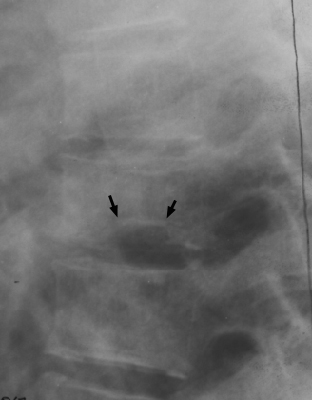

Lateral radiographs of the spine reveals central endplate depression with sparing of the anterior and posterior margins of the endplate. Several current names have been ascribed to these same changes seen in patients with hemoglobinopathy, such as Lincoln Log Sign, or H-shaped vertebra. Although not pathognomonic, these terms are typically reserved for a patient with Sickle-Cell disease.